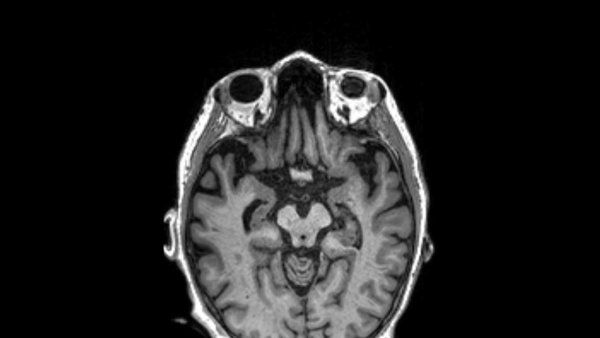

PET scan of a brain